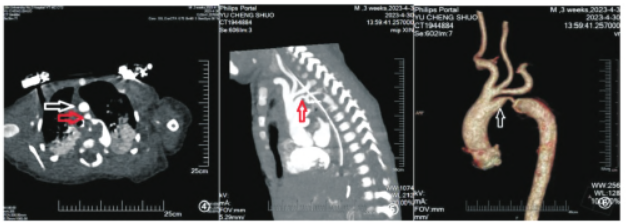

主动脉弓降部管腔限局性缩窄(图④,⑤),直径约为2.0mm,长度约为2.8mm,动脉导管闭塞,肺动脉侧可见动脉圆锥残留,头臂干,左侧颈总动脉,左侧锁骨下动脉共干(图⑥)。房间隔缺损。腹主动脉上段直径约为6.8mm。双肺可见斑片状密度增高影结论:主动脉弓降部管腔限局性缩窄,动脉导管闭塞,缩窄段远端、近缩窄处低密度充盈缺损,头臂干、左侧颈总动脉、左侧锁骨下动脉共干,房间隔缺损,双肺炎症。

图4-6 主动脉CTA 检查:图④横断位主动脉CTA,可见第四主动脉弓(白色箭头所示),第五主动脉弓及与其相连的降主动脉(红色箭头所示);图⑤矢状位MIP图,箭头所示可见降主动脉管腔限局性缩窄;图⑥VR 彩图,箭头所示为永存第五主动脉弓,并可见发出三大分支(头臂干,左侧颈总动脉,左侧锁骨下动脉)的第四弓。